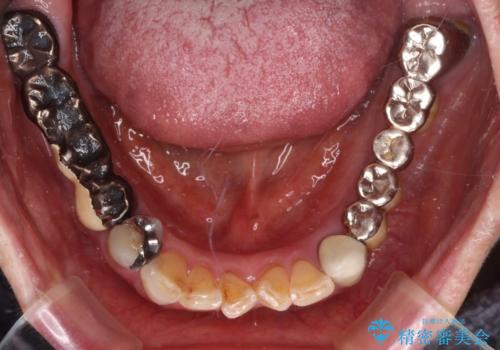

処置を予定していた歯を仮歯に変えた時点で、下顎前歯の部分矯正を行うかどうかを尋ねたところ、折角なので行いたいと言うことでしたので、矯正治療を行うこととしました。

インプラント埋入や根管治療治療など、治癒に一定の期間を要する処置の合間に矯正治療を行うことで、効率的に治療を進めて行くことができました。